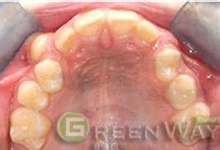

3、 个性化设计更有效。隐形矫治技术继承了传统的牙颌畸形矫治理念,是现代口腔医学、计算机辅助三维诊断、个性化设计及数字化成型技术的完美结合,是正畸领域的新突破。据介绍,隐形矫冶采用的是完全个性化的设计理念,每一个矫治器都是为患者专门设计,通过三维诊断软件,医生还可以在矫治前在计算机上模拟临床上的牙齿移动方式,逐步达到矫治目标,也让患者更清楚地感受到矫治后的完美形象,从而实现了错合畸形矫治模拟过程及结果的三维可视化。然后,再结合先进的三维激光快速成形技术,制作出每个矫治阶段的透明压模隐形矫治器。